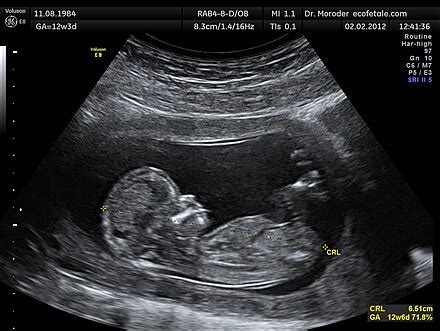

- Kombinált szűrés: A terhesség első harmadában (11-13. hét) végzett ultrahangvizsgálat (tarkóredő vastagságának mérése) és az anyai vérből vett mintában két biokémiai jelző (marker) meghatározása (szabad béta hCG és PAPP-A).

- Ultrahangvizsgálat: A magzati fejlődés során bizonyos eltérések (pl. nyaki redő, alaki és méretbeli eltérések, szívrendellenességek) észlelhetők, amelyek felkelthetik a Down-szindróma gyanúját.